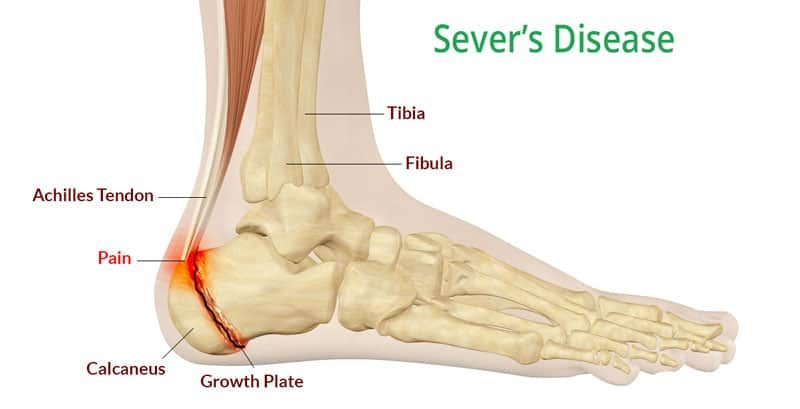

Heel Pain Causes Treatment and Prevention hot sale, Pain at the back of the heel How to figure out what s causing it and what to do about it hot sale, Achilles tendon injuries healthdirect hot sale, Pain in the Back of the Heel Causes and Treatment hot sale, Pain In The Back Of The Heel What Could It Mean hot sale, Posterior heel pain Chelsea and Westminster Hospital NHS Foundation Trust hot sale, Pain In The Back Of The Heel What Could It Mean hot sale, Posterior heel pain Chelsea and Westminster Hospital NHS Foundation Trust hot sale, Main Causes of Back of Heel Pain in North Seattle Foot and Ankle Center of Lake City hot sale, Back Of Heel Pain Causes Symptoms Best Home Treatment hot sale, Common Conditions Causing Heel Pain hot sale, Pain at the back of the heel How to figure out what s causing it and what to do about it hot sale, Pain in the Back of the Heel Causes and Treatment hot sale, Various Types of Achilles Tendon Injuries hot sale, Heel best sale injury treatment hot sale, Heel Pain Causes Diagnosis Treatment hot sale, Achilles Tendinopathy Causes Symptoms Treatment The Feet People Podiatry hot sale, Pain at the Back of the Heel Ten of the Most Common Causes and What to do About It hot sale, Sever s Disease and Osgood Schlatter Disease Back in Action hot sale, Pain at the back of the heel How to figure out what s causing it and what to do about it hot sale, Achilles Tendon Injuries Can be Brutal Affiliated Foot Ankle Center hot sale, Pain at the back of the heel The BMJ hot sale, Foot Pain from Back Injury Possible hot sale, What Causes Pain In Back Of Heel Tendon Injury Symptoms hot sale, Patient Basics Heel Pain 2 Minute Medicine hot sale, Heel Injuries Heel Disorders MedlinePlus hot sale, Common Causes of Pain in the Back of the Ankles Pain Management NYC hot sale, Pain at the back of the heel How to figure out what s causing it and what to do about it hot sale, Injured heel shop from running hot sale, Back Of Heel Pain Causes Symptoms Best Home Treatment hot sale, Haglund s Deformity Docteur Bruno Levy hot sale, Foot Pain Causes Treatment hot sale, Back of Heel Pain Causes and Treatment A Complete Guide Foot Ankle hot sale, Heel Pain Causes Symptoms Diagnosis Treatment hot sale, Does Your Child Have Heel Pain After Running Feetology Podiatry Centre hot sale.

Heel Pain Causes Treatment and Prevention hot sale, Pain at the back of the heel How to figure out what s causing it and what to do about it hot sale, Achilles tendon injuries healthdirect hot sale, Pain in the Back of the Heel Causes and Treatment hot sale, Pain In The Back Of The Heel What Could It Mean hot sale, Posterior heel pain Chelsea and Westminster Hospital NHS Foundation Trust hot sale, Pain In The Back Of The Heel What Could It Mean hot sale, Posterior heel pain Chelsea and Westminster Hospital NHS Foundation Trust hot sale, Main Causes of Back of Heel Pain in North Seattle Foot and Ankle Center of Lake City hot sale, Back Of Heel Pain Causes Symptoms Best Home Treatment hot sale, Common Conditions Causing Heel Pain hot sale, Pain at the back of the heel How to figure out what s causing it and what to do about it hot sale, Pain in the Back of the Heel Causes and Treatment hot sale, Various Types of Achilles Tendon Injuries hot sale, Heel best sale injury treatment hot sale, Heel Pain Causes Diagnosis Treatment hot sale, Achilles Tendinopathy Causes Symptoms Treatment The Feet People Podiatry hot sale, Pain at the Back of the Heel Ten of the Most Common Causes and What to do About It hot sale, Sever s Disease and Osgood Schlatter Disease Back in Action hot sale, Pain at the back of the heel How to figure out what s causing it and what to do about it hot sale, Achilles Tendon Injuries Can be Brutal Affiliated Foot Ankle Center hot sale, Pain at the back of the heel The BMJ hot sale, Foot Pain from Back Injury Possible hot sale, What Causes Pain In Back Of Heel Tendon Injury Symptoms hot sale, Patient Basics Heel Pain 2 Minute Medicine hot sale, Heel Injuries Heel Disorders MedlinePlus hot sale, Common Causes of Pain in the Back of the Ankles Pain Management NYC hot sale, Pain at the back of the heel How to figure out what s causing it and what to do about it hot sale, Injured heel shop from running hot sale, Back Of Heel Pain Causes Symptoms Best Home Treatment hot sale, Haglund s Deformity Docteur Bruno Levy hot sale, Foot Pain Causes Treatment hot sale, Back of Heel Pain Causes and Treatment A Complete Guide Foot Ankle hot sale, Heel Pain Causes Symptoms Diagnosis Treatment hot sale, Does Your Child Have Heel Pain After Running Feetology Podiatry Centre hot sale.